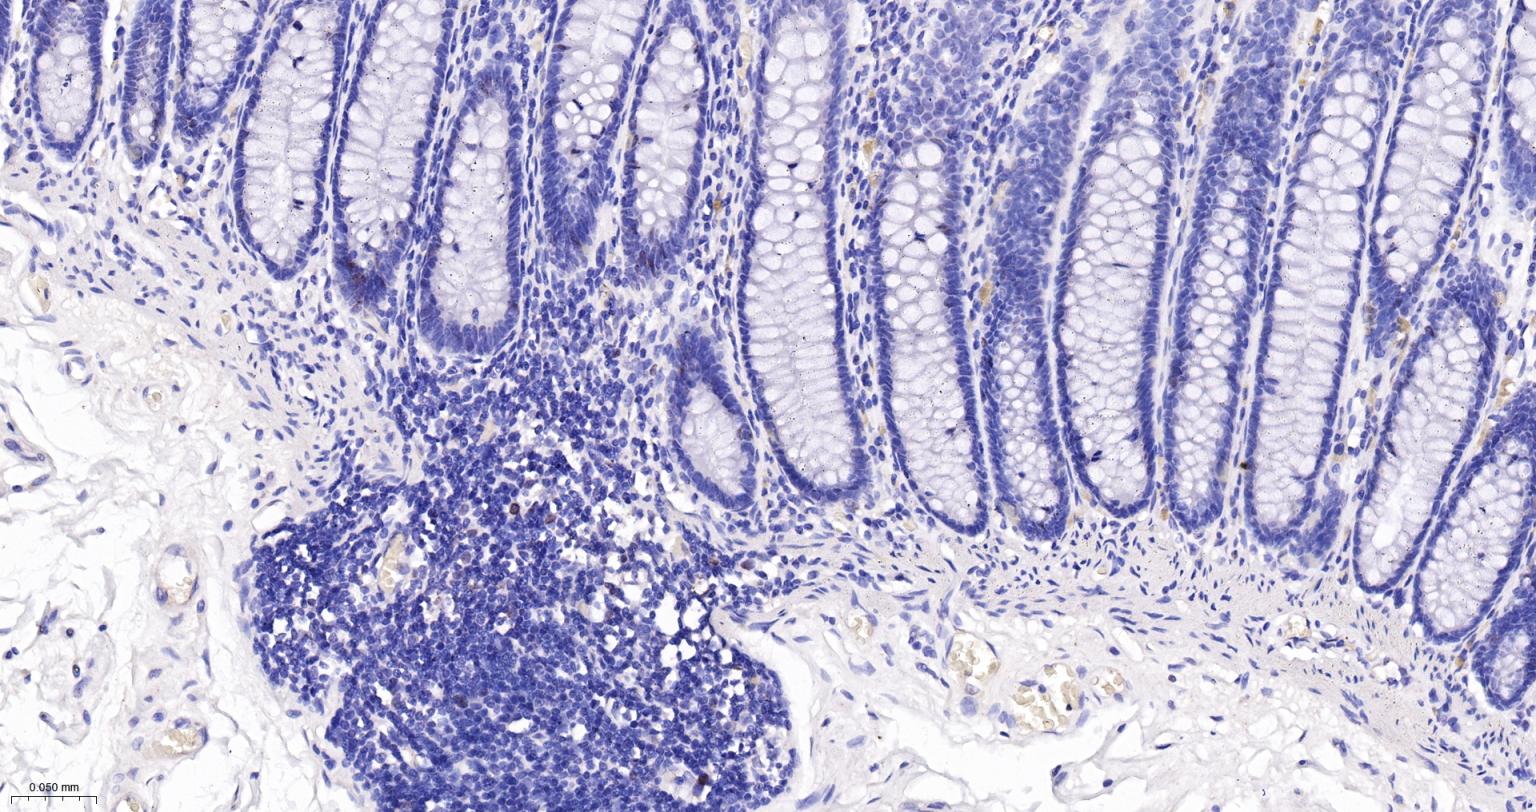

IHC-PHuman, RatMouse1:100-500

IHC-FHuman, RatMouse1:100-500

Ki67与PCNA一样,为细胞增殖的一种标记,在细胞凋亡中S、G2 、M期均有表达,G0期缺如。

Ki-67增殖指数高低与许多肿瘤的分化程度、浸润、转移以及预后密切相关,因此被广泛作为各种恶性肿瘤的必检项目之一。

Ki67 antigen is the prototypic cell cycle related nuclear protein, expressed by proliferating cells in all phases of the active cell cycle (G1, S, G2 and M phase). It is absent in resting (G0) cells. Ki67 antibodies are useful in establishing the cell growing fraction in neoplasms (immunohistochemically quantified by determining the number of Ki67 positive cells among the total number of resting cells = Ki67 index). In neoplastic tissues the prognostic value is comparable to the tritiated thymidine labelling index. The correlation between low Ki67 index and histologically low grade tumours is strong. Ki67 is routinely used as a neuronal marker of cell cycling and proliferation.